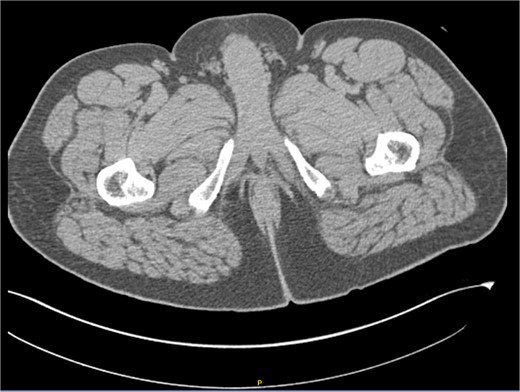

After receiving the pathology report, an abdominal computed tomography (CT) scan with intravenous contrast was ordered (Fig. 3). The analysis revealed diffuse distribution of hepatic cystic lesions, with diameters of up to 5 mm, which did not enhance with contrast. Additionally, it was observed that the perianal region showed no fat stranding or increased volume, and no lymphadenopathy was detected.

Computed tomography (CT) scan with intravenous contrast (IV). Hepatic cystic lesions, with diameters of up to 5 mm, which did not enhance with contrast. Additionally, it was observed that the perianal region showed no fat stranding or increased volume, and no lymphadenopathy was detected.